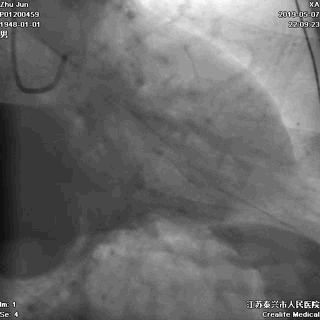

冠脉左主干线样狭窄

回旋支主支中段闭塞

前降支开口次全闭塞

至此,症状、心电图结合冠状动脉造影检查结果,该患者“急性心肌梗死”诊断明确,冠脉造影提示血栓向主干延伸,病情非常危重,死亡风险极大,需要紧急行心脏介入手术。讲明疾病风险和手术风险后,患方很快接受介入手术。